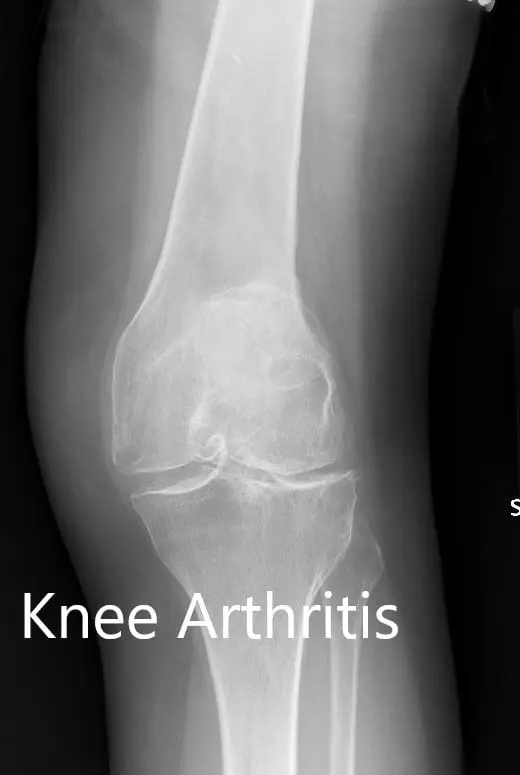

Preoperative X-ray showing the AP view of the left and the right knee respectively

Preoperative X-ray showing the AP view of the left and the right knee respectively - img 2